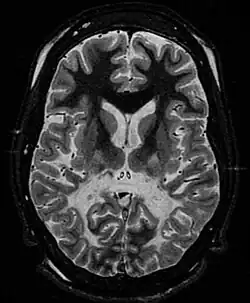

White matter, with reduced volume and increased signal intensity. The anterior white matter is spared. Features are consistent with X-linked adrenoleukodystrophy. | |